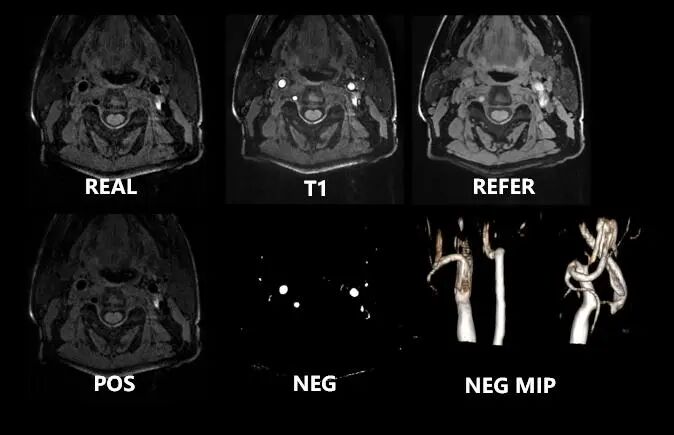

02  SNAP

gre_snap 序列是基于3D gre_fsp,由一个IR翻转脉冲内的两个采集窗构成;同时集成了TOF与gre_fsp技术的功能,具有成像速度快,空间分辨力高,图像对比度强,检测特异性好的优点,可以重建图像:Real、T1、Refer、Pos、Neg。可以提供高质量的头颈部血管成像。

联影磁共振怎么样更先进、更高效、更精准—联影3.0T超导磁共振落户武城县人民医院_https://www.jmylbn.com_新闻资讯_第14张